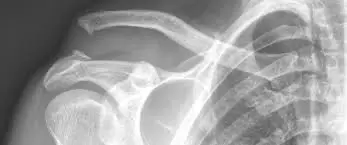

A vizsgálat alapja a fizikális vizsgálat és a röntgen. Az AC sérülések megítélésére gyakran készül:

• váll/AC ízületi röntgen felvétel (különböző irányokból)

• összehasonlító felvétel a másik oldalról (bizonyos esetekben)

• ritkábban ultrahang vagy MRI (szalagok, társult sérülések tisztázására)

A súlyosságot sokszor a Rockwood-besorolás írja le (I–VI), amely segít a kezelési döntésekben.

Az AC ízületi luxatio (vállcsúcsi ízületi ficam) olyan sérülés, amikor a kulcscsont (clavicula) és a lapocka vállcsúcsi nyúlványa (acromion) közötti ízület stabilitása sérül, leggyakrabban vállra esés vagy sportbaleset után. A panaszok tipikusan vállcsúcsi fájdalomduzzanat/véraláfutásmozgásbeszűkülés, és súlyosabb esetben látványos deformitás (a kulcscsont vége „kiállhat”, kialakulhat „lépcső” jellegű eltérés). A diagnózis alapja az orvosi vizsgálat és a röntgen, szükség esetén ultrahang vagy MRI is szóba jöhet. A sérülés súlyosságát gyakran a Rockwood-besorolás (I–VI) alapján határozzák meg, ami a kezelési döntéseket is segíti.